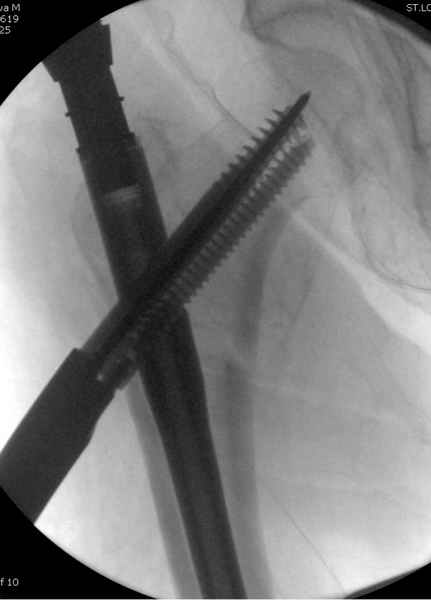

В общем, сделали. См. приложение.

Длина и из-за этого ось получились не совсем такие, как хотелось бы, все-таки срок после той операции уже 6 недель. Может быть, стоило провести дистракцию аппаратом неделю-другую. Заранее спасибо за комментарии и критику.